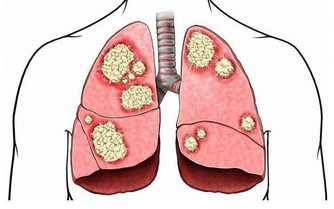

4. 呼吸急促

呼吸不暢或呼吸急促,特別是伴有疲勞或胸痛時,可能表明有心臟問題。

有些女性在躺下時可能會感到呼吸不暢,而在坐直時得以緩和。